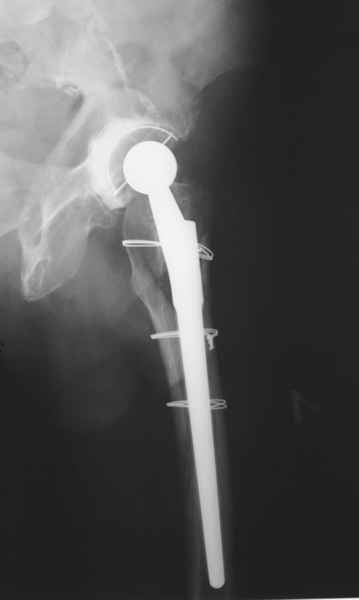

2. Применение ножки дистальной фиксации, мы отдаем предпочтение ножке Вагнера с фиксацией проксимального отдела на ножке. Более травматичное вмешательство, но при стабильной фиксации ножки реабилитация идет в обычном режиме.

Хочется показать два подобных случая, П-ка З. 72 лет и п-т Г. 80 лет. Сразу принимаю замечание, что это были ножки цементной фиксации, просто под руками не было бесцементника.

Частично правильный ответ - 1. Это В-2 перелом (проксимальный отдел скорее жив, чем мертв). Костная пластика кортикальными трансплантатами необходима. Также необходим остеосинтез большим количеством проволочных металлических серкляжей. Пластина не нужна.

Используя ножку "Вагнер", как советует Рашид Муртазалиевич получите хорошую фиксацию по каналу, качественную адаптацию отломков, экономию финансов.

Мы, в нашем отделении, именно при таких переломах, обходимся без костной пластики. Установив ножку Вагнер ревизионный в дистальный отдел бедренной кости, костные отломки адаптируем вокруг ножки и фиксируем проволочным серкляжом или Cable-Ready "Zimmer".